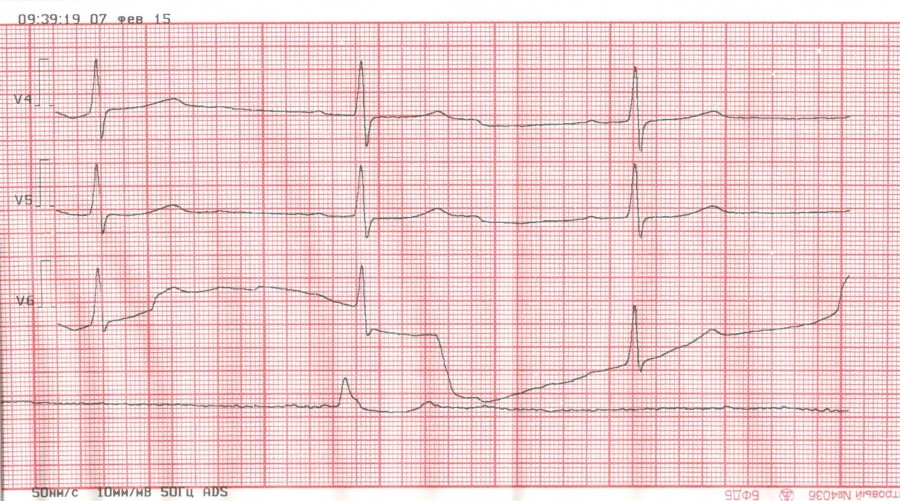

Нижний инфаркт с полной А-В блокадой

Изображение

Обсуждалось здесь viewtopic.php?f=11&t=7873&p=76998#p76998